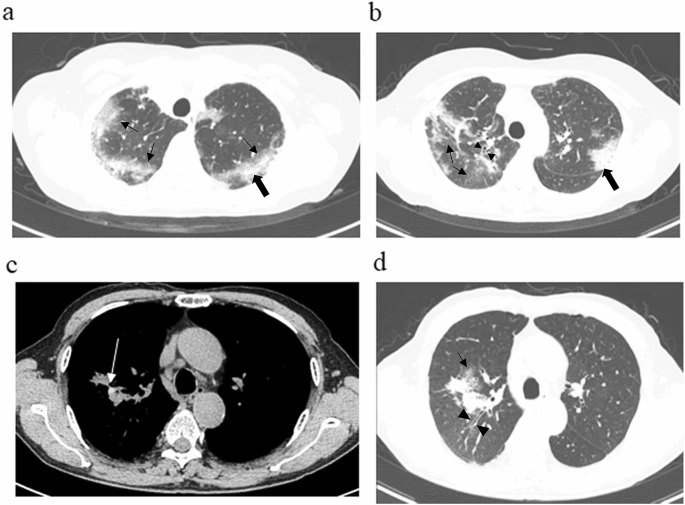

This retrospective cohort study from a single center included 25 outpatients (median age, 65 years) with ABPA diagnosed between April 2015 and March 2019, using criteria proposed by the International Society of Human and Animal Mycology (ISHAM), which focuses on positive specific IgE for Aspergillus fumigatus. Patients were assigned to either the eosinophilic pneumonia (EP) group or Non-EP group, defined according to findings on high-resolution computed tomography (HRCT). The EP group included patients with HRCT findings compatible with CEP; i.e., the presence of peripheral consolidation (p-consolidation) or ground-glass opacities (GGO), with no evidence of high-attenuation mucus. The Non-EP group comprised the remaining patients, who showed classical findings of ABPA such as mucoid impaction. Differences between the groups were analyzed.